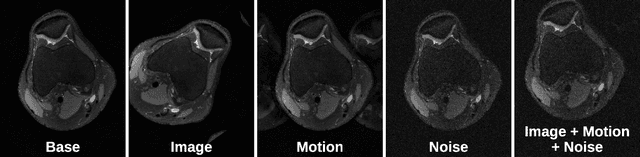

Abstract:Deep neural networks have enabled improved image quality and fast inference times for various inverse problems, including accelerated magnetic resonance imaging (MRI) reconstruction. However, such models require large amounts of fully-sampled ground truth data, which are difficult to curate and are sensitive to distribution drifts. In this work, we propose applying physics-driven data augmentations for consistency training that leverage our domain knowledge of the forward MRI data acquisition process and MRI physics for improved data efficiency and robustness to clinically-relevant distribution drifts. Our approach, termed VORTEX (1) demonstrates strong improvements over supervised baselines with and without augmentation in robustness to signal-to-noise ratio change and motion corruption in data-limited regimes; (2) considerably outperforms state-of-the-art data augmentation techniques that are purely image-based on both in-distribution and out-of-distribution data; and (3) enables composing heterogeneous image-based and physics-driven augmentations.